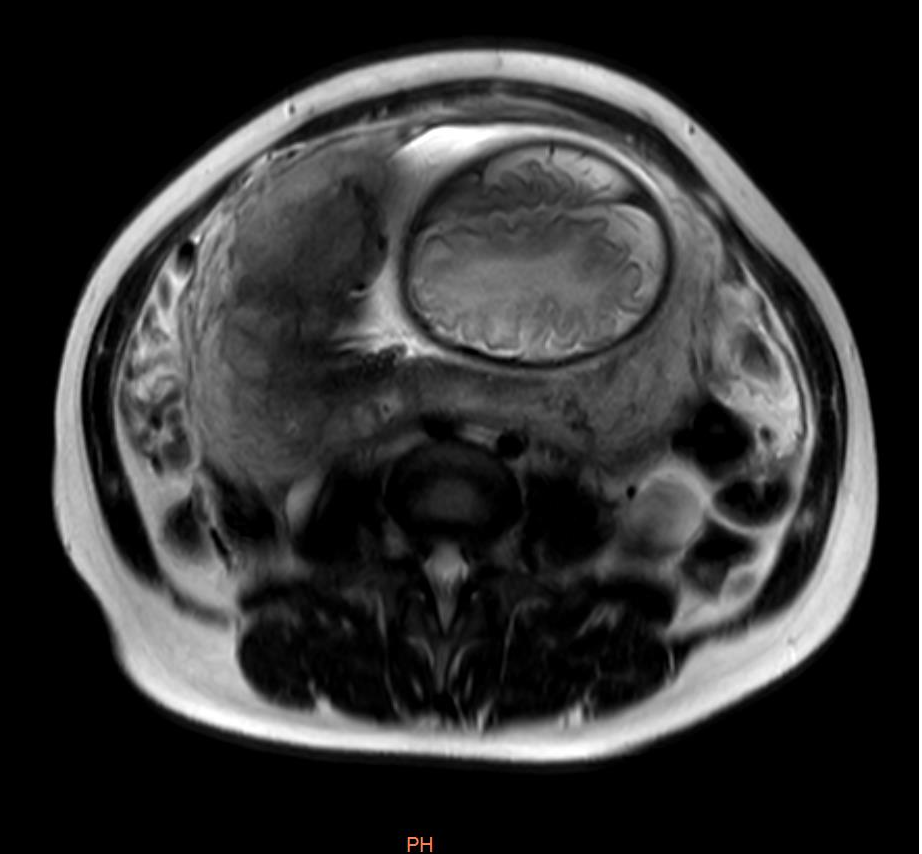

影像显示:前置胎盘并胎盘植入

了解情况后,影像科应用飞利浦3.0T超导磁共振迅速为患者进行了检查,影像科技术人员操作熟练、检查细致规范,图像多方位采集,清晰显示患者病情,影像科医师阅片与检查同步进行,认真及时分析图像,发现郭女士为胎盘前置,完全覆盖宫颈管内口,胎盘与子宫剖宫产术后瘢痕分解不清,胎盘下见粗大血管影及少量出血信号,存在胎盘植入。

前置胎盘并胎盘植入影像

前置胎盘并发胎盘植入是产科严重的并发症,常引起大出血,甚至休克,增加子宫切除率,严重危及产妇及胎儿安全。据悉,前置胎盘患者并发胎盘植入的发生率高达50%。术前准确诊断可指导手术方案的制定,因此,及时准确的诊断对孕产妇至关重要。目前,前置胎盘并胎盘植入的影像诊断主要依据经腹超声探查,但该方法易受孕妇及胎盘位置的影响,诊断准确率较不固定。MRI快速扫描技术发展迅速,已逐步应用于胎盘疾病的诊断。